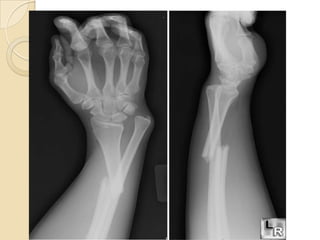

 RAIO-X : deve incluir sempre a articulação do

cotovelo e do punho